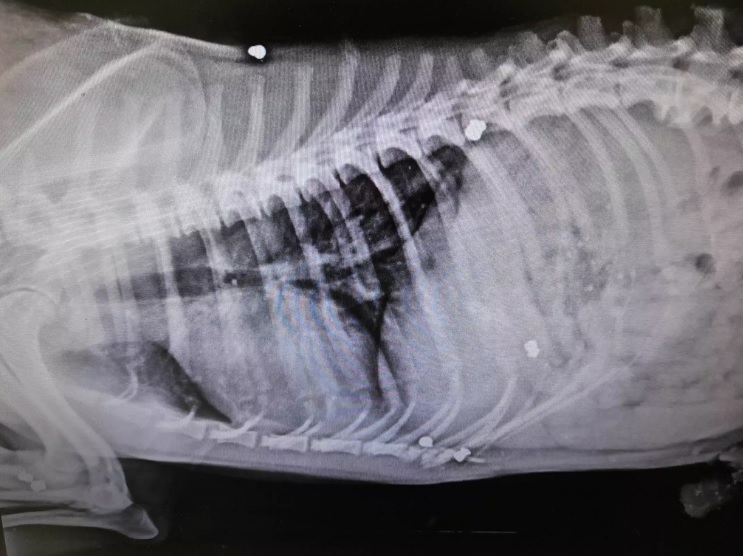

Όλα έγιναν το πρωί της Δευτέρας 20 Μαρτίου του 2023 στο Ψυχικό στις Σέρρες. Όπως αναφέρει σε ανάρτησή του ο Φιλοζωικός Σύλλογος Εμμανουήλ Παππά, ο αδέσποτος σκύλος Smiley, δέχθηκε τουλάχιστον 10 πυροβολισμούς από αεροβόλο όπλο που κρατούσε στα χέρια του ασυνείδητος κάτοικος του χωριού, με αποτέλεσμα να βρει φρικτό θάνατο.

Μάλιστα, το άψυχο σώμα του σκύλου εντοπίστηκε πεταμένο στα σκουπίδια. Ο νεκρός σκύλος μεταφέρθηκε σε κτηνιατρείο αλλά παρά τις προσπάθειες που έγιναν δεν επανήλθε στη ζωή. Η κοινωνία στις Σέρρες, παραμένει ανάστατη από τα όσα έγιναν, με τους αστυνομικούς να προσπαθούν να φτάσουν στα ίχνη του δράστη, μέσα από μαρτυρίες αλλά και οι εικόνες που κατέγραψαν οι κάμερες ασφαλείας της περιοχής.